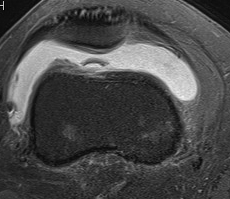

MRI

Demonstrates

- MPFL tear

- cartilage damage

- loose body